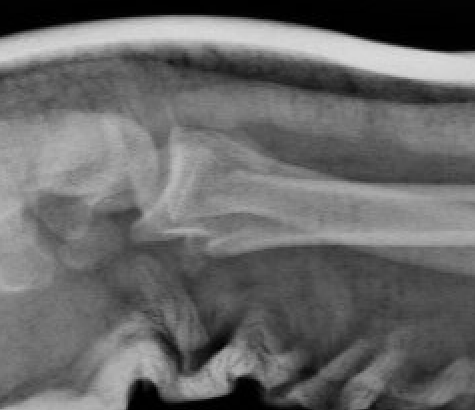

Smith's Fracture

- distal radial fracture with volar displacement

- need long arm cast in supination

Distal Radius Smiths Fracture